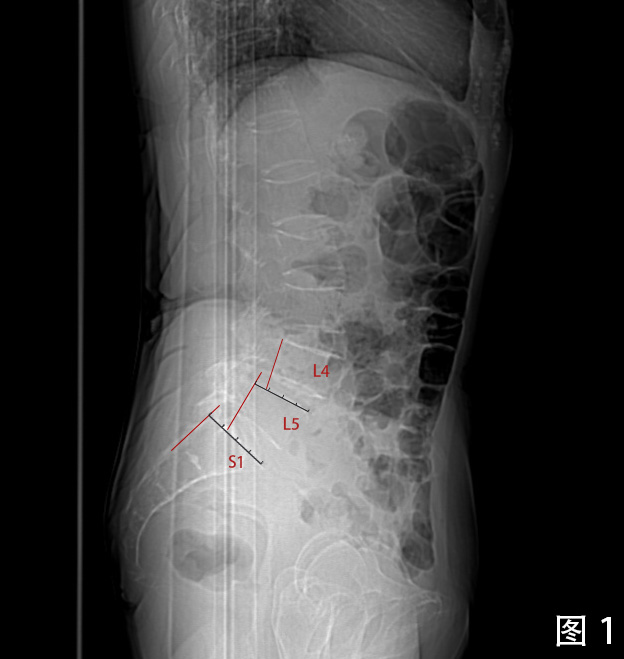

专科检查:2022-08-17 腰椎CT平扫检查阅片:腰椎椎体序列不稳定,椎管内可见增生钙化,继发椎管骨性狭窄。根据Meyerding分级, L4椎体向前I度滑脱,L5椎体向前II度滑脱,为连续2个节段的退行性滑脱(图1)。L3/4、L4/5、L5/S1椎间盘膨出,硬膜囊受压。L4、L5椎体小关节增生硬化明显,相应节段竖脊肌萎缩。椎间盘于相邻椎体层面以相反方向超出椎体边缘“夹心征”(图2)。L5椎体假关节形成(图3)。